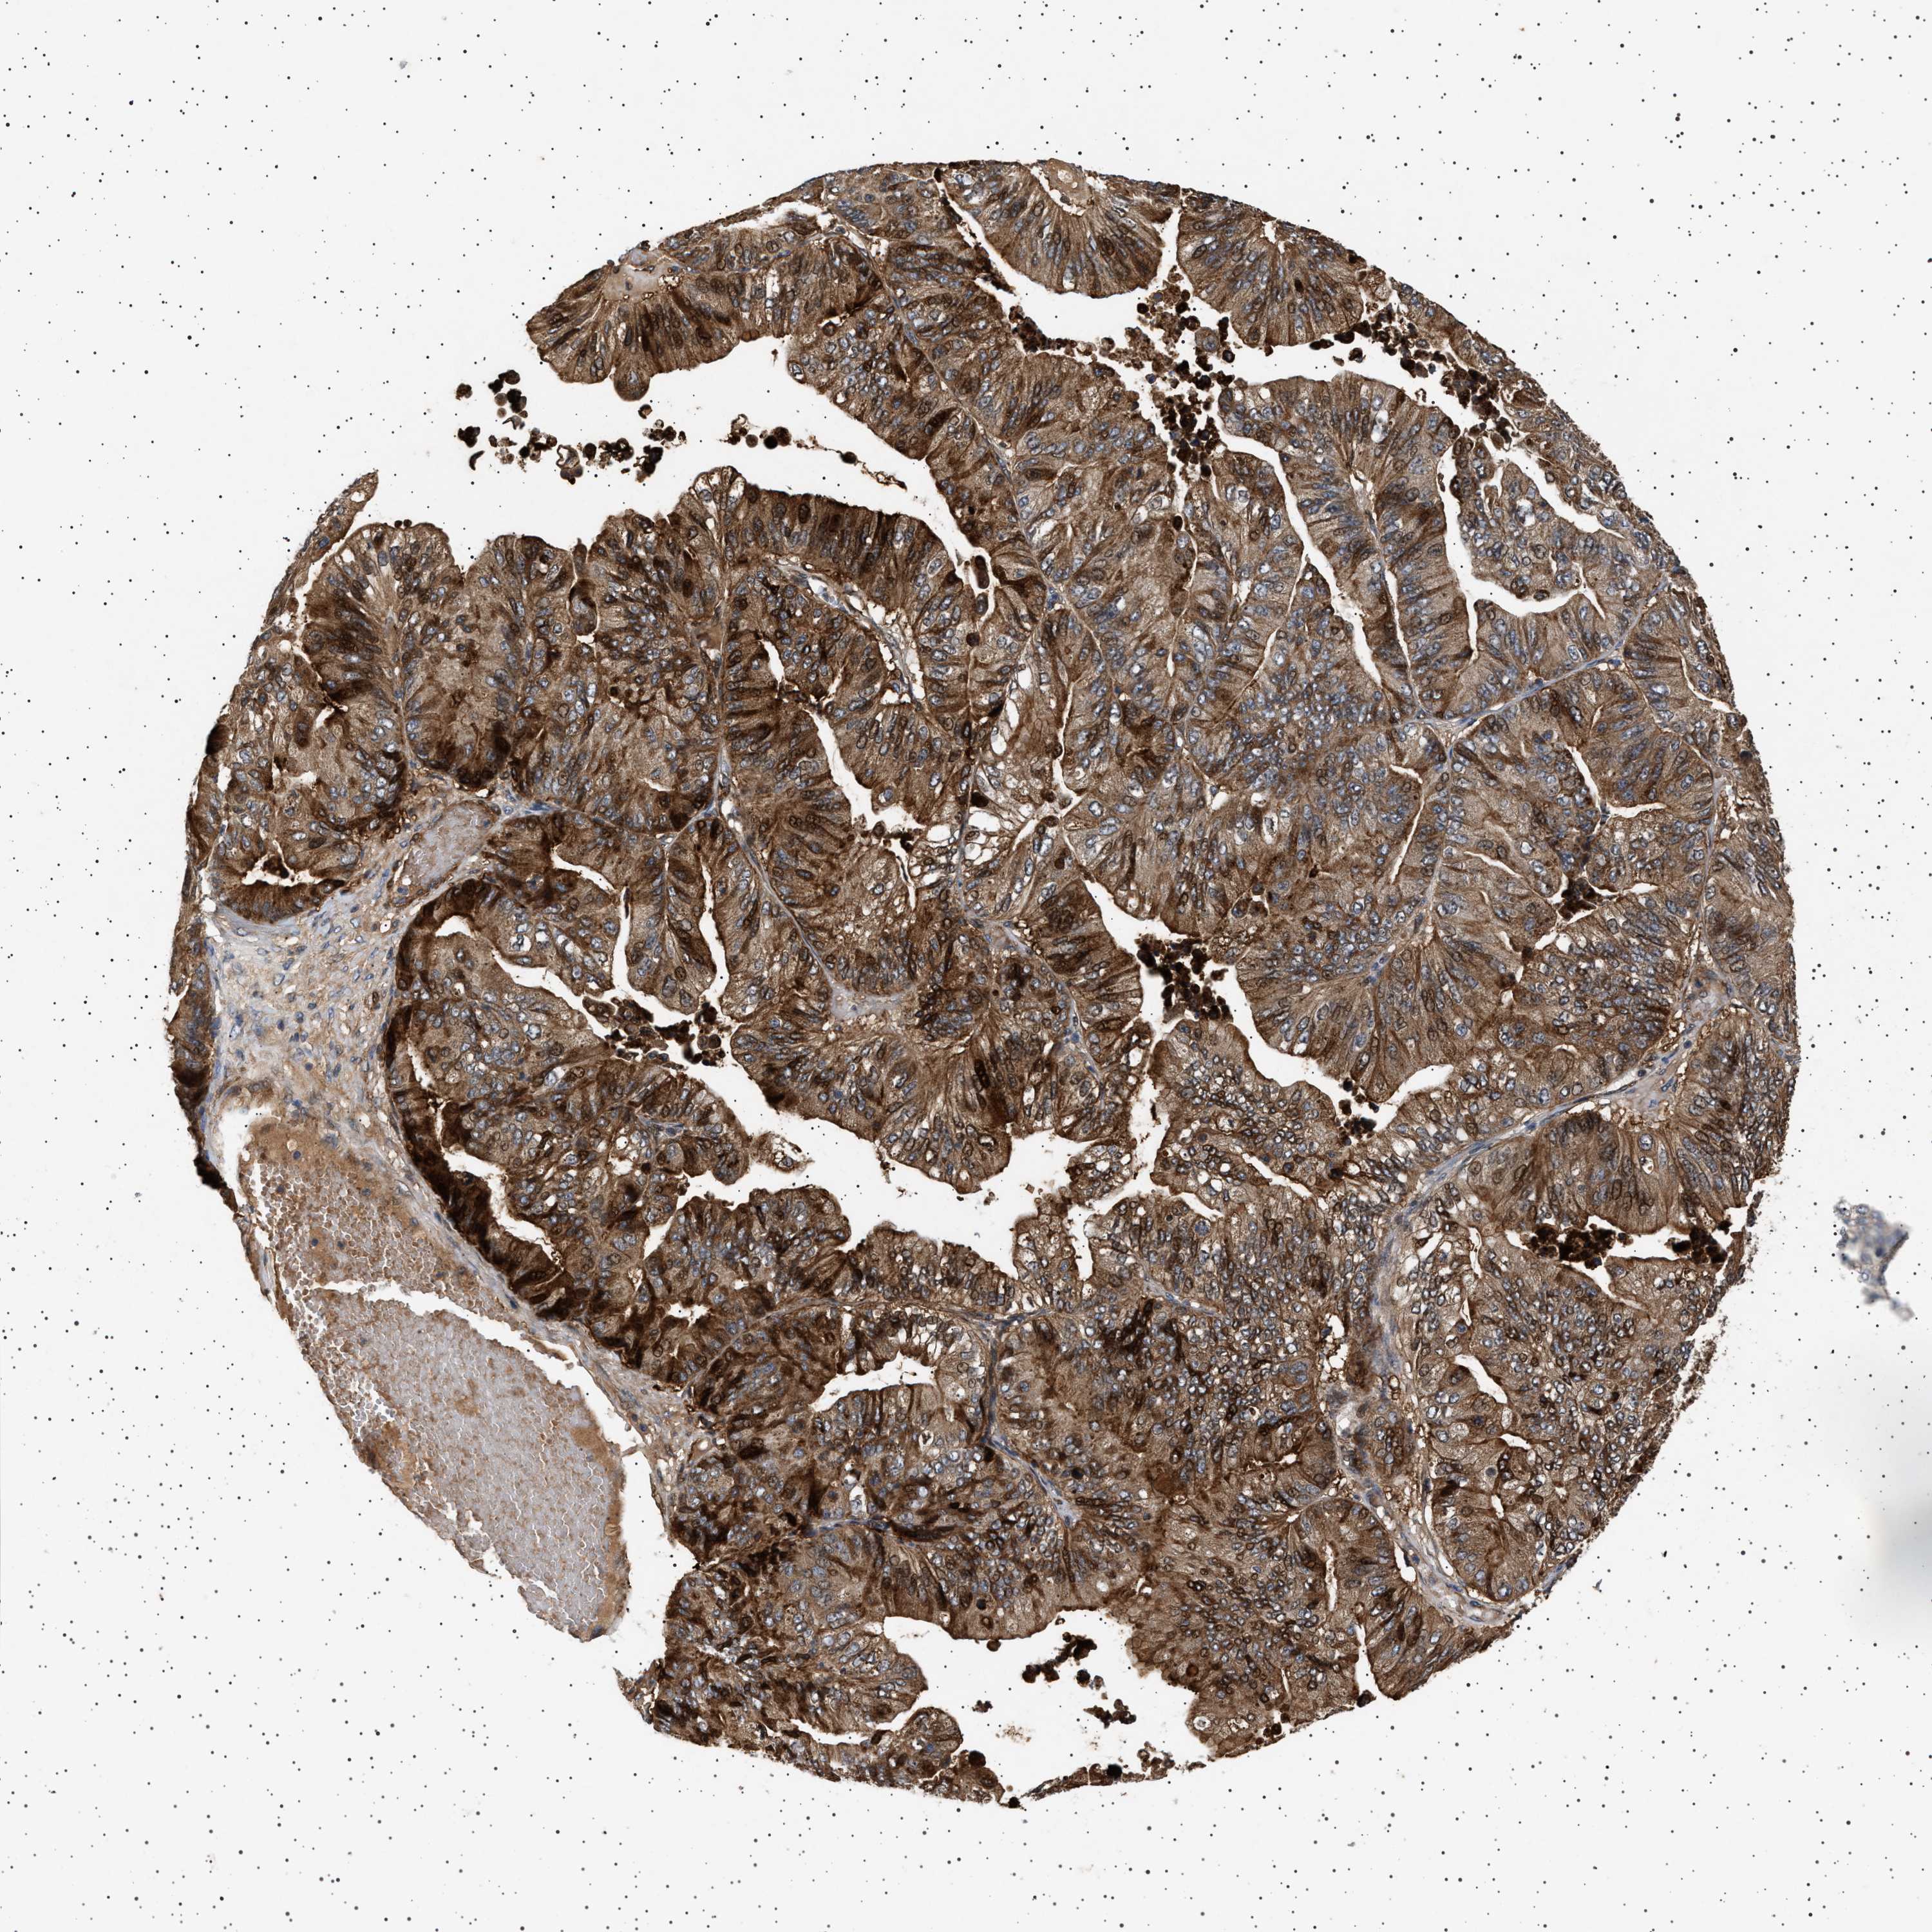

OVARIAN CANCER - Protein expressioni

A mouse-over function shows sample information and annotation data. Click on an image to view it in a full screen mode. Samples can be filtered based on level of antibody staining by selecting one or several of the following categories: high, medium, low and not detected. The assay and annotation is described here.

Note that samples used for immunohistochemistry by the Human Protein Atlas do not correspond to samples in the TCGA dataset.

Antibody stainingi

Antibody staining in the annotated cell types in the current human tissue is reported as not detected, low, medium, or high, based on conventional immunohistochemistry profiling in selected tissues. This score is based on the combination of the staining intensity and fraction of stained cells.

Each image is clickable and will lead to virtual microscopy that enables deeper exploration of all samples and also displays staining intensity scores, fraction scores and subcellular localization as well as patient and tissue information for each sample.

Antibody HPA020870

Antibody CAB010890

Cystadenocarcinoma, serous, NOS

Carcinoma, endometroid

Cystadenocarcinoma, mucinous, NOS

Carcinoma, NOS